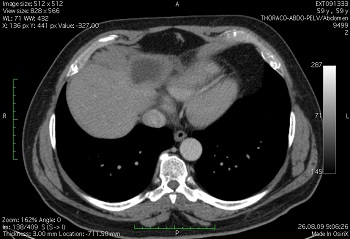

Рентгеновская компьютерная томография (КТ) является современным и точным диагностическим методом, который позволяет в кратчайшие сроки получить информацию о состоянии того или иного органа человека. В результате — послойная 3D-реконструкция необходимого изображения. В ходе процедуры аппарат совершает указанное количество излучений, делая так называемые «срезы» — изображения тонких слоев органа. Его можно просматривать и масштабировать (увеличить или уменьшить), выделяя зоны интереса.

Компьютерная томография печени является важным диагностическим инструментом, позволяющим врачам получить детализированные изображения органа и выявить различные патологии. Специалисты отмечают, что данный метод помогает в диагностике опухолей, цирроза, гепатитов и других заболеваний. Качество изображений позволяет оценить размеры, структуру и состояние печени, что критически важно для выбора правильной тактики лечения.

Компьютерная томография печени позволяет определить состояние ткани органа, визуализировать различные новообразования, установить причину геатомегалии или желтухи. Кроме этого, КТ давно является ведущим методом при травмах живота, так как в кратчайшие сроки показывает наиболее точную картину.

Изображение на томограмме зависит от уровня слоя и плотности (HU) выделяемых объектов. Нормальная картина может отличаться у разных людей в соответствии с индивидуальными особенностями строения, но имеются такие общие признаки:

- Ткань печени (паренхима) однородна;

- Ее плотность превышает таковую у близлежащих органов;

- Печень имеет ровные, резкие контуры и края;

- На фоне паренхимы могут визуализироваться сосуды, плотность которых значительно ниже;

- На уровне 11-12 грудных позвонков (иногда его дно достигает 4-5 поясничных) определяется желчный пузырь.

Патологические изменения могут носит как очаговый, так и диффузный (распространенный) характер, поэтому те или иные особенности визуализации отличаются при разных заболеваниях.

О патологии можно судить по следующим признакам:

- Контуры печени нечеткие, бугристые;

- Четко визуализируются новообразования. О некоторых доброкачественных опухолях мы судим по очаговому снижению плотности паренхимы;

- Наличие камней;

- Гепатоз характеризуется низкой плотностью паренхимы;

- Изменение размеров печени;

- Сосудистые изменения в сочетании с неоднородностью паренхимы может свидетельствовать о цирротическом процессе;

- Определение варикозно-расширенных вен – признак портальной гипертензии;

- Свободная жидкость в брюшной полости (асцит);

- Кисты имеют вид округлых образований с ровным контуром и жидкостью внутри. Абсцесс имеет схожие признаки, однако вокруг него определяется также зона измененной вследствие воспаления ткани, а его плотностью несколько выше;

- Гепатома (рак) имеет вид ограниченного дефекта неправильной формы с нечеткими контурами;

- Лучевая картина метастазов может быть различна, что обусловлено количеством и размером опухолевых узлов.